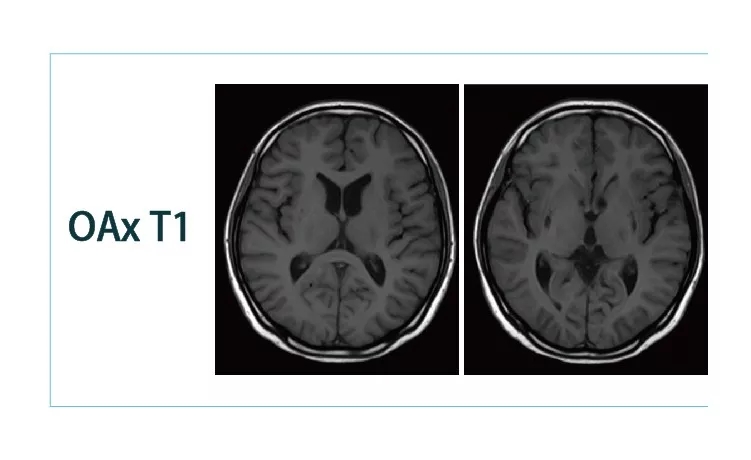

【朗润影像档案】20181130磁共振影像病例结果讨论